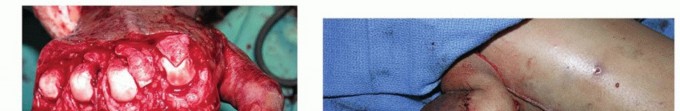

In cases involving severe crush injuries or burns, the overlying skin and subcutaneous tissues may be contracted, lacking the necessary elasticity to accommodate the newly restored joint motion. If the skin blanches or tears upon passive flexion (in MCP release) or extension (in PIP release), the surgeon must immediately address the soft tissue envelope. Forcing the joint into position under a tight skin closure will inevitably lead to wound breakdown, infection, and recurrent, more severe stiffness.

Local tissue rearrangements, such as Z-plasties or V-Y advancements, can provide minor gains in longitudinal length. However, significant skin deficits require the importation of healthy, vascularized tissue. Full-thickness skin grafts may be utilized if a healthy, vascularized paratenon or muscle bed is present. In the presence of exposed tendon or bone devoid of periosteum, a local or regional flap, such as a cross-finger flap, a reverse flow homodigital island flap, or even a free tissue transfer, becomes mandatory. The reconstructive ladder must be respected to ensure a durable, supple envelope that facilitates, rather than hinders, postoperative rehabilitation.